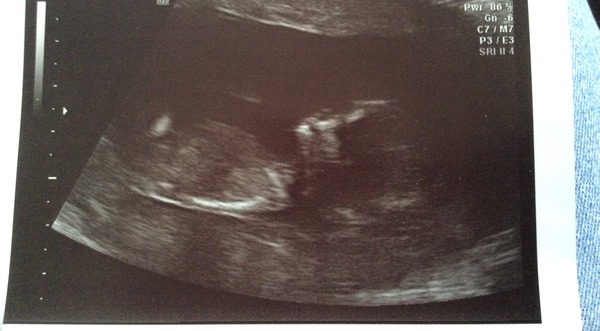

Hello! Saw baby Olaf today! 12 weeks and 2 days although I'm still sticking with my Christmas Eve due date, did the nucheal fold test as well which looks good apparently so thats good to hear

What a lovely image Smile

Wow three scans today! Olaf looks so serene and placid that photo is beautiful.

Thanks cuppa but my scan was last week so was only 10 weeks and 5 so tthe photo wasn't great have another next week though ar 12 weeks and 5 going with a normal bladder so I can enjoy it more your picture is lovely Ohholyfuck so clear.